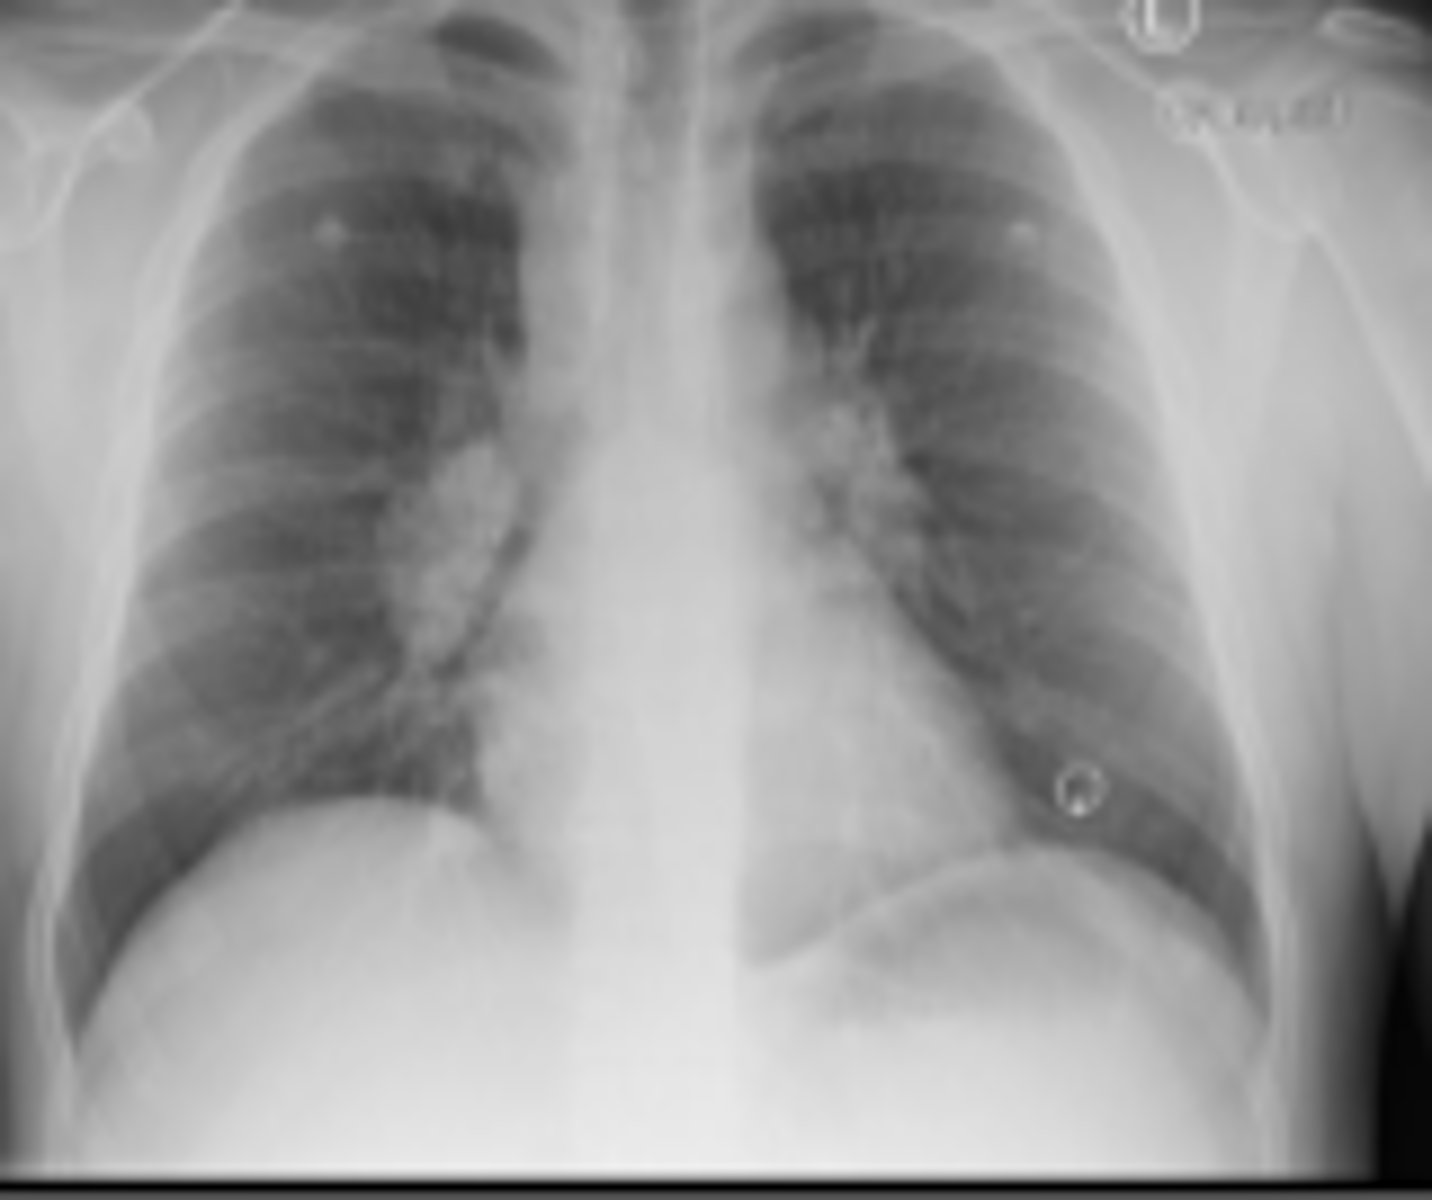

What is seen of CXR with TB?

- unilateral apical infiltrates

- caseating granulomas

- cavitations

- Ghon complexes

- pleural effusion

What is seen on CXR with sarcoidosis, and what is stage I/ IV?

- I: hilar lymphadenopathy

- IV: overt pulmonary fibrosis